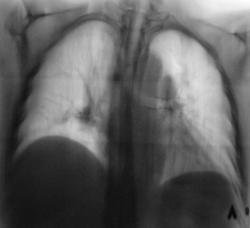

Картина ампутации левого нижнедолевого бронха, ателектаз нижней доли слева, диссеминация метастатической природы

Левый главный бронх оттеснен кверху, по всей видимости, за счет увеличения л/узлов бифуркационной группы?

Теперь о данном наблюдении. Оценка рентгенограмм к сожалению очень индивидуальный и субъективный процесс. Ход моих мыслей: пожилой пациент без жалоб, а на снимках выраженная диффузная патология в грудной клетке - сразу включается механизм перехода мышления на онкологические рельсы. Я много лет работал в детской торакальной хирургии, поэтому так насторожен и "кидаюсь" на малейшие смещения средостения - мне показалось, что есть смещение сердца влево. Конечно, лучше, чтобы снимок был чуть более жестким, и на нем не было бы абсолютно непрозрачных мест, но что имеем...

Внутри тени сердца, параллельно контуру левого желудочка внизу есть дополнительный контур, который я расценил как наружную границу уменьшенной левой нижней доли, отсюда и все мои последующие выводы. Именно эти места уже отмечены Вами желтыми стрелками - просто наши оценки одного и того же различаются. Насчет четкой видимости ампутации бронха - согласен, двоечтение возможно.

В литературе и на практике встречал 3 основных варианта картины ателектаза нижней доли слева. Для всех них в прямой проекции характерно легкое смешение сердца влево, повление интенсивной треугольной тени за сердцем слева медиально, второго контура за сердцем. Но в боковой проекции картина разнообразна (в какой плоскости преимущесвенно сложится доля - как веер) и сводится к трем основным вариантам:

В отличии от уважаемых коллег, я не увидел признаков ателектаза ни слева, ни справа, при этом согласен с наличием диффузных изменений, в сочетании с увеличением лимфоузлов в обоих корнях. Диф. ряд весьма широк.